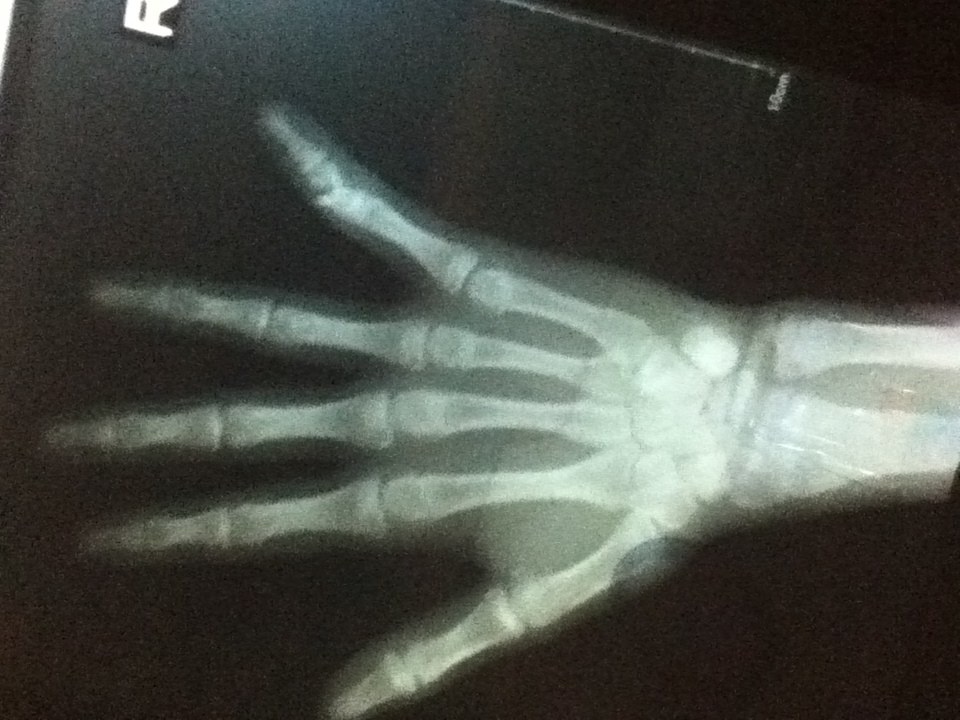

月曜日に小指の針金を抜いた息子1は、手術した病院から「最初に見てもらった病院でリハビリしてねー」と紹介状を持って最初に行った病院に翌日出向いた。

明日、息子1の指から針金が抜かれます。

息子1、明日10:30から手術やってさ。